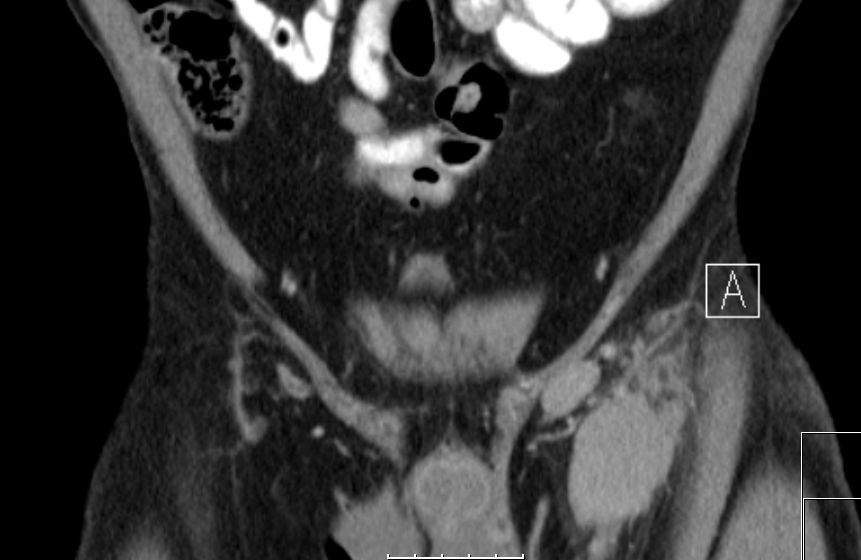

Mesenterialer Bulk |

77-jähriger Mann mit einem abdominalen Tumor und Stenosesymptomatik. Im Dünndarmresektat mit Mesenterialwurzel ein follikuläres Lymphom Grad II-IIIa, FLIPI-Score 2.![]() |